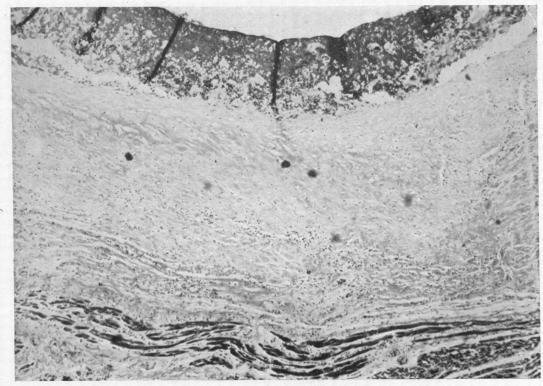

DAVIES J N, BALL J D

Br Heart J. 1955 Jul;17(3):337-59. doi: 10.1136/hrt.17.3.337.